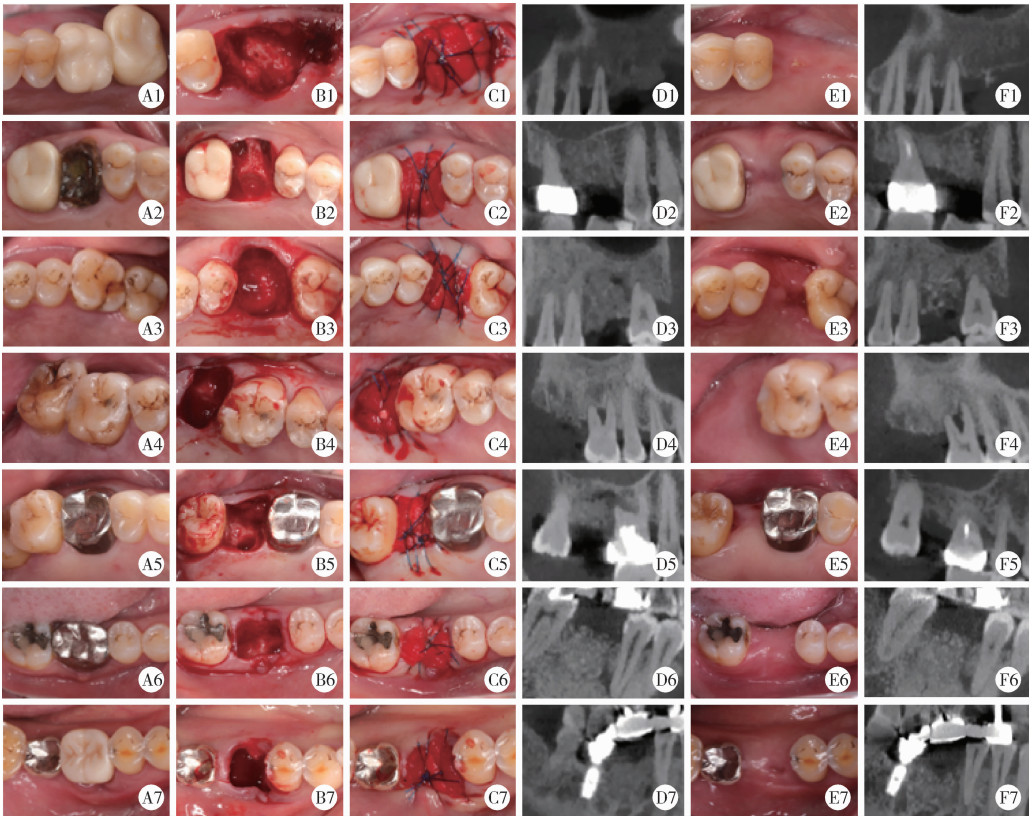

Clinical photographs and CBCT cross-sectional images of DBBM group at different time points A1-A7, preoperative occlusal view; B1-B7, tooth socket; C1-C7, immediate postoperative occlusal view; D1-D7, immediate postoperative CBCT; E1-E7, 6 months follow-up; F1-F7; CBCT taken 6 months postoperative. Abbreviations as in Figure 2."

Figure 4

Clinical photographs and CBCT cross-sectional images of HA group at different time points A1-A7, preoperative occlusal view; B1-B7, tooth socket; C1-C7, immediate postoperative occlusal view; D1-D7, immediate postoperative CBCT; E1-E7, 6 months follow-up; F1-F7; CBCT taken 6 months postoperative. Abbreviations as in Figure 2."